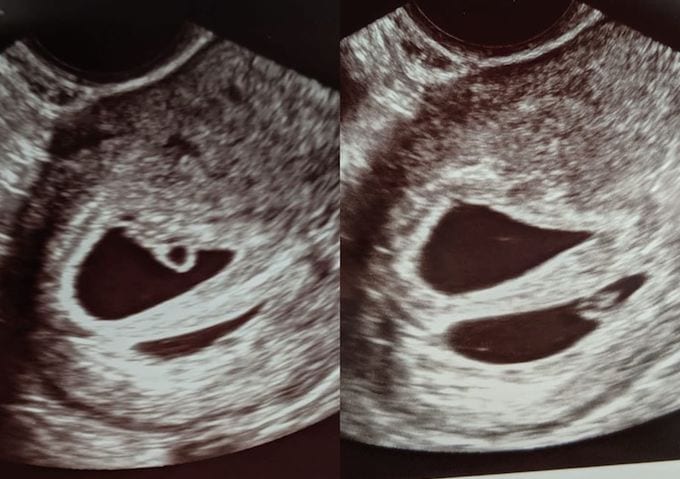

What Does an Ultrasound Look like at 6 Weeks Pregnant With Twins?

At four to five weeks after a pregnant woman’s last period the ultrasound commonly shows a small collection of fluid within the lining of the uterus that represents the early development of the gestational sac. At about five and a half weeks after a pregnant woman’s last period the ultrasound typically shows a gestational sac and within it we can see a 3-5 mm bubble-like structure, which is the yolk sac. At approximately six weeks after a pregnant woman’s last period, we can see a small fetal pole, one of the first stages of growth for an embryo, which develops alongside the yolk sac. UT Southwestern Medical Center

Yes! You’d need to have an ultrasound at 6 weeks to confirm a twin pregnancy. Your twin belly at 6 weeks may not look like much of a belly at all, so getting in to your doctor for an ultrasound is key to find out if you’re really having twins.